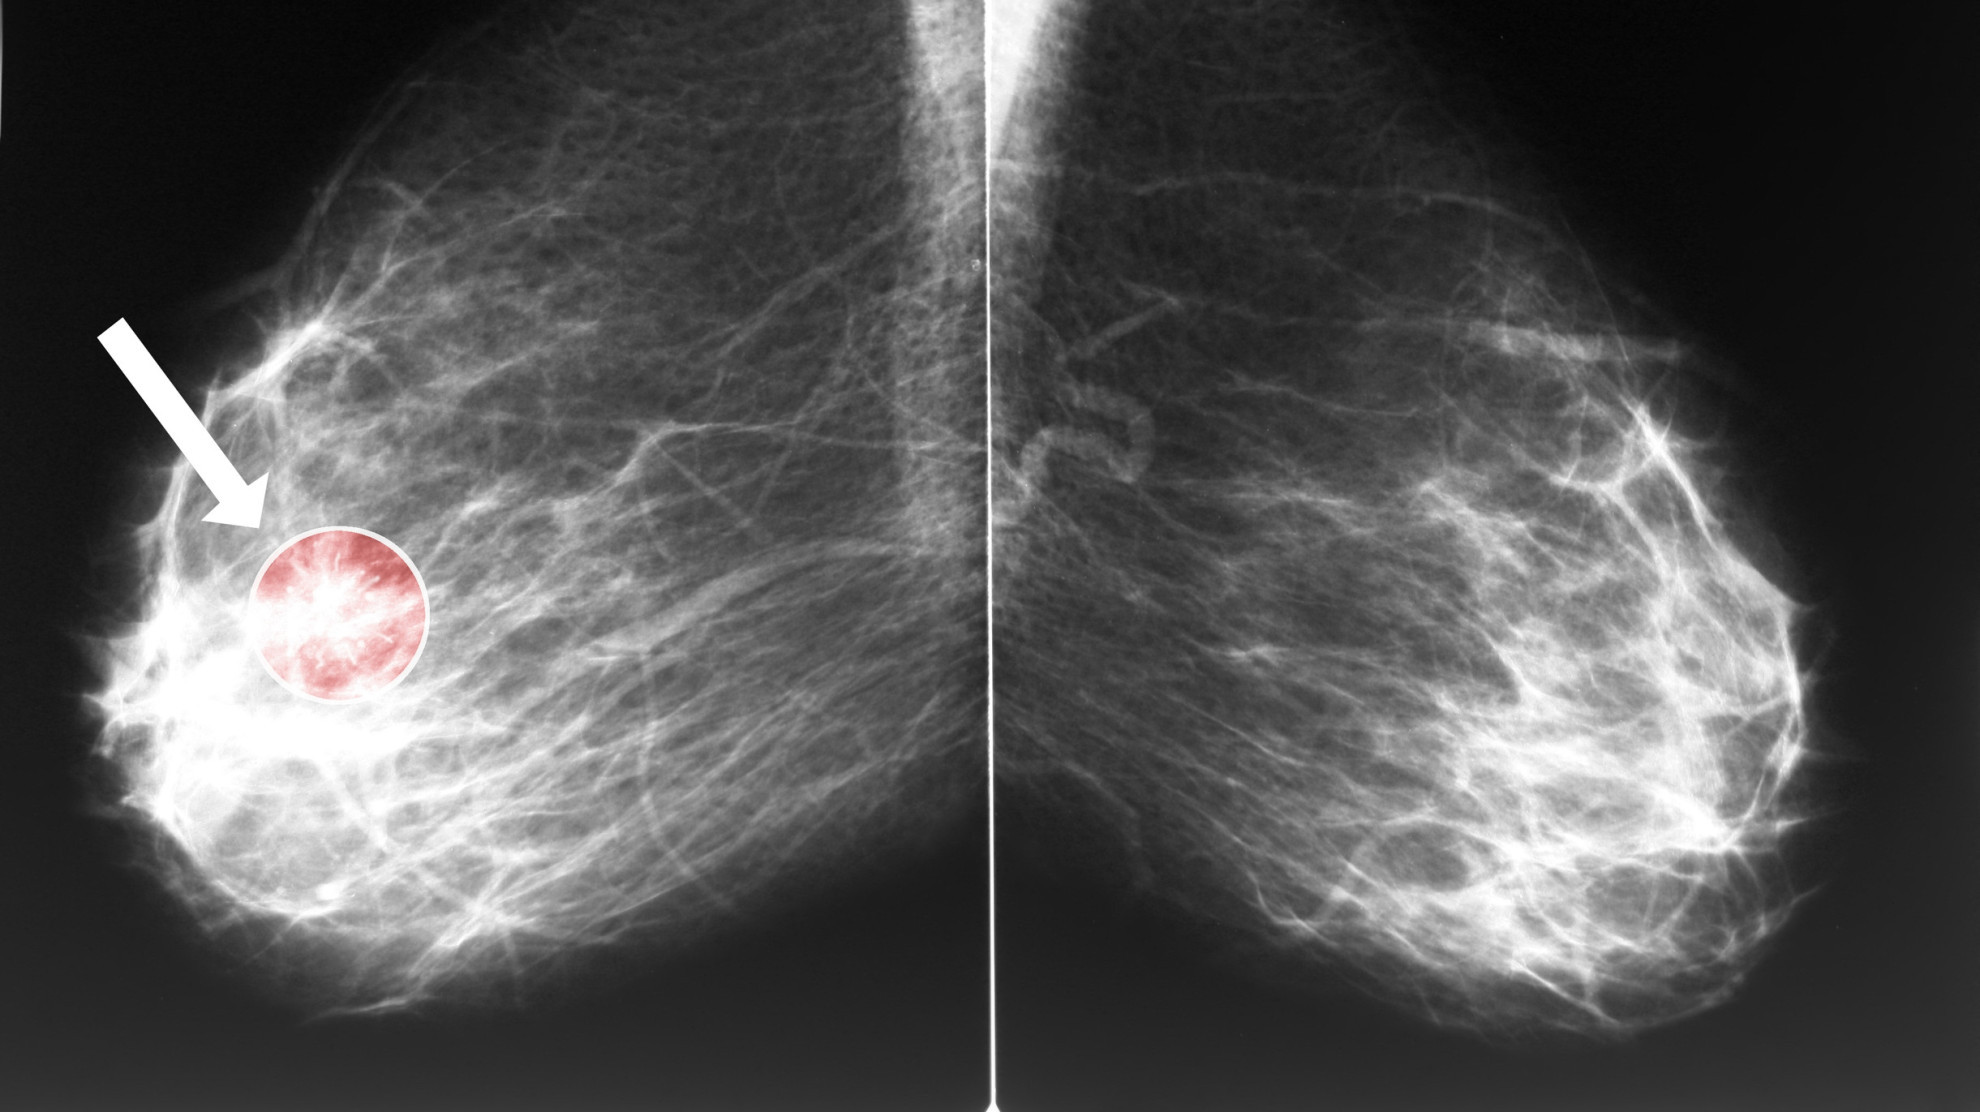

Ученые из Манчестерского университета оценили выживаемость и частоту развития рака молочной железы у носителей мутаций BRCA1 и BRCA2 без онкологического анамнеза, выбравших профилактическую мастэктомию или наблюдение. Результаты исследования опубликованы в Journal of Clinical Oncology.

Анализ показал, что ежегодная частота развития рака молочной железы составила 2,4% в группе наблюдения и 0,15% после профилактической мастэктомии, что соответствует снижению риска появления опухоли на 94%. Во время операции выявили девять скрытых случаев рака, что составило 2% от числа прооперированных.

| Анализировали данные 1205 женщин с патогенными вариантами BRCA1 и BRCA2 без рака молочной железы в анамнезе. Оценивали общую выживаемость, специфическую для рака молочной железы выживаемость и ежегодную заболеваемость. Наблюдение проводили с использованием методов визуализации в соответствии с национальными рекомендациями. |

Авторы заключили, что у носителей мутаций BRCA профилактическая мастэктомия и структурированное наблюдение обеспечивают сходную общую и специфическую выживаемость в среднесрочной перспективе. При этом хирургическое вмешательство значительно снижает частоту развития рака молочной железы, что важно учитывать при индивидуальном выборе тактики.